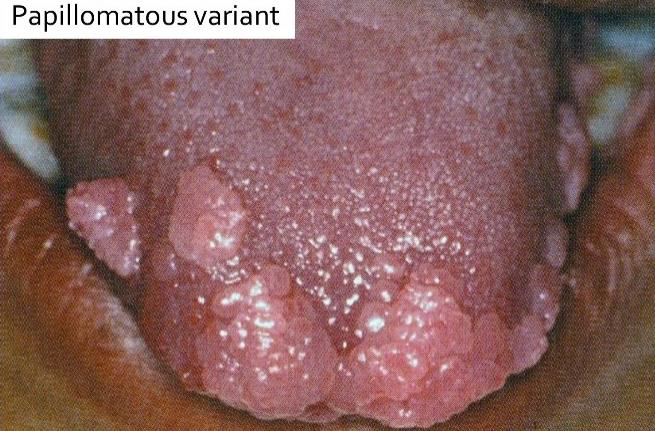

| Multifocal epithelial hyperplasia (Heck’s disease, 13, 32) |

低社經、HIV | 唇、頰、舌 | 小、軟、多、無痛 | |||

Papillomatous variant

|

Papulonodular